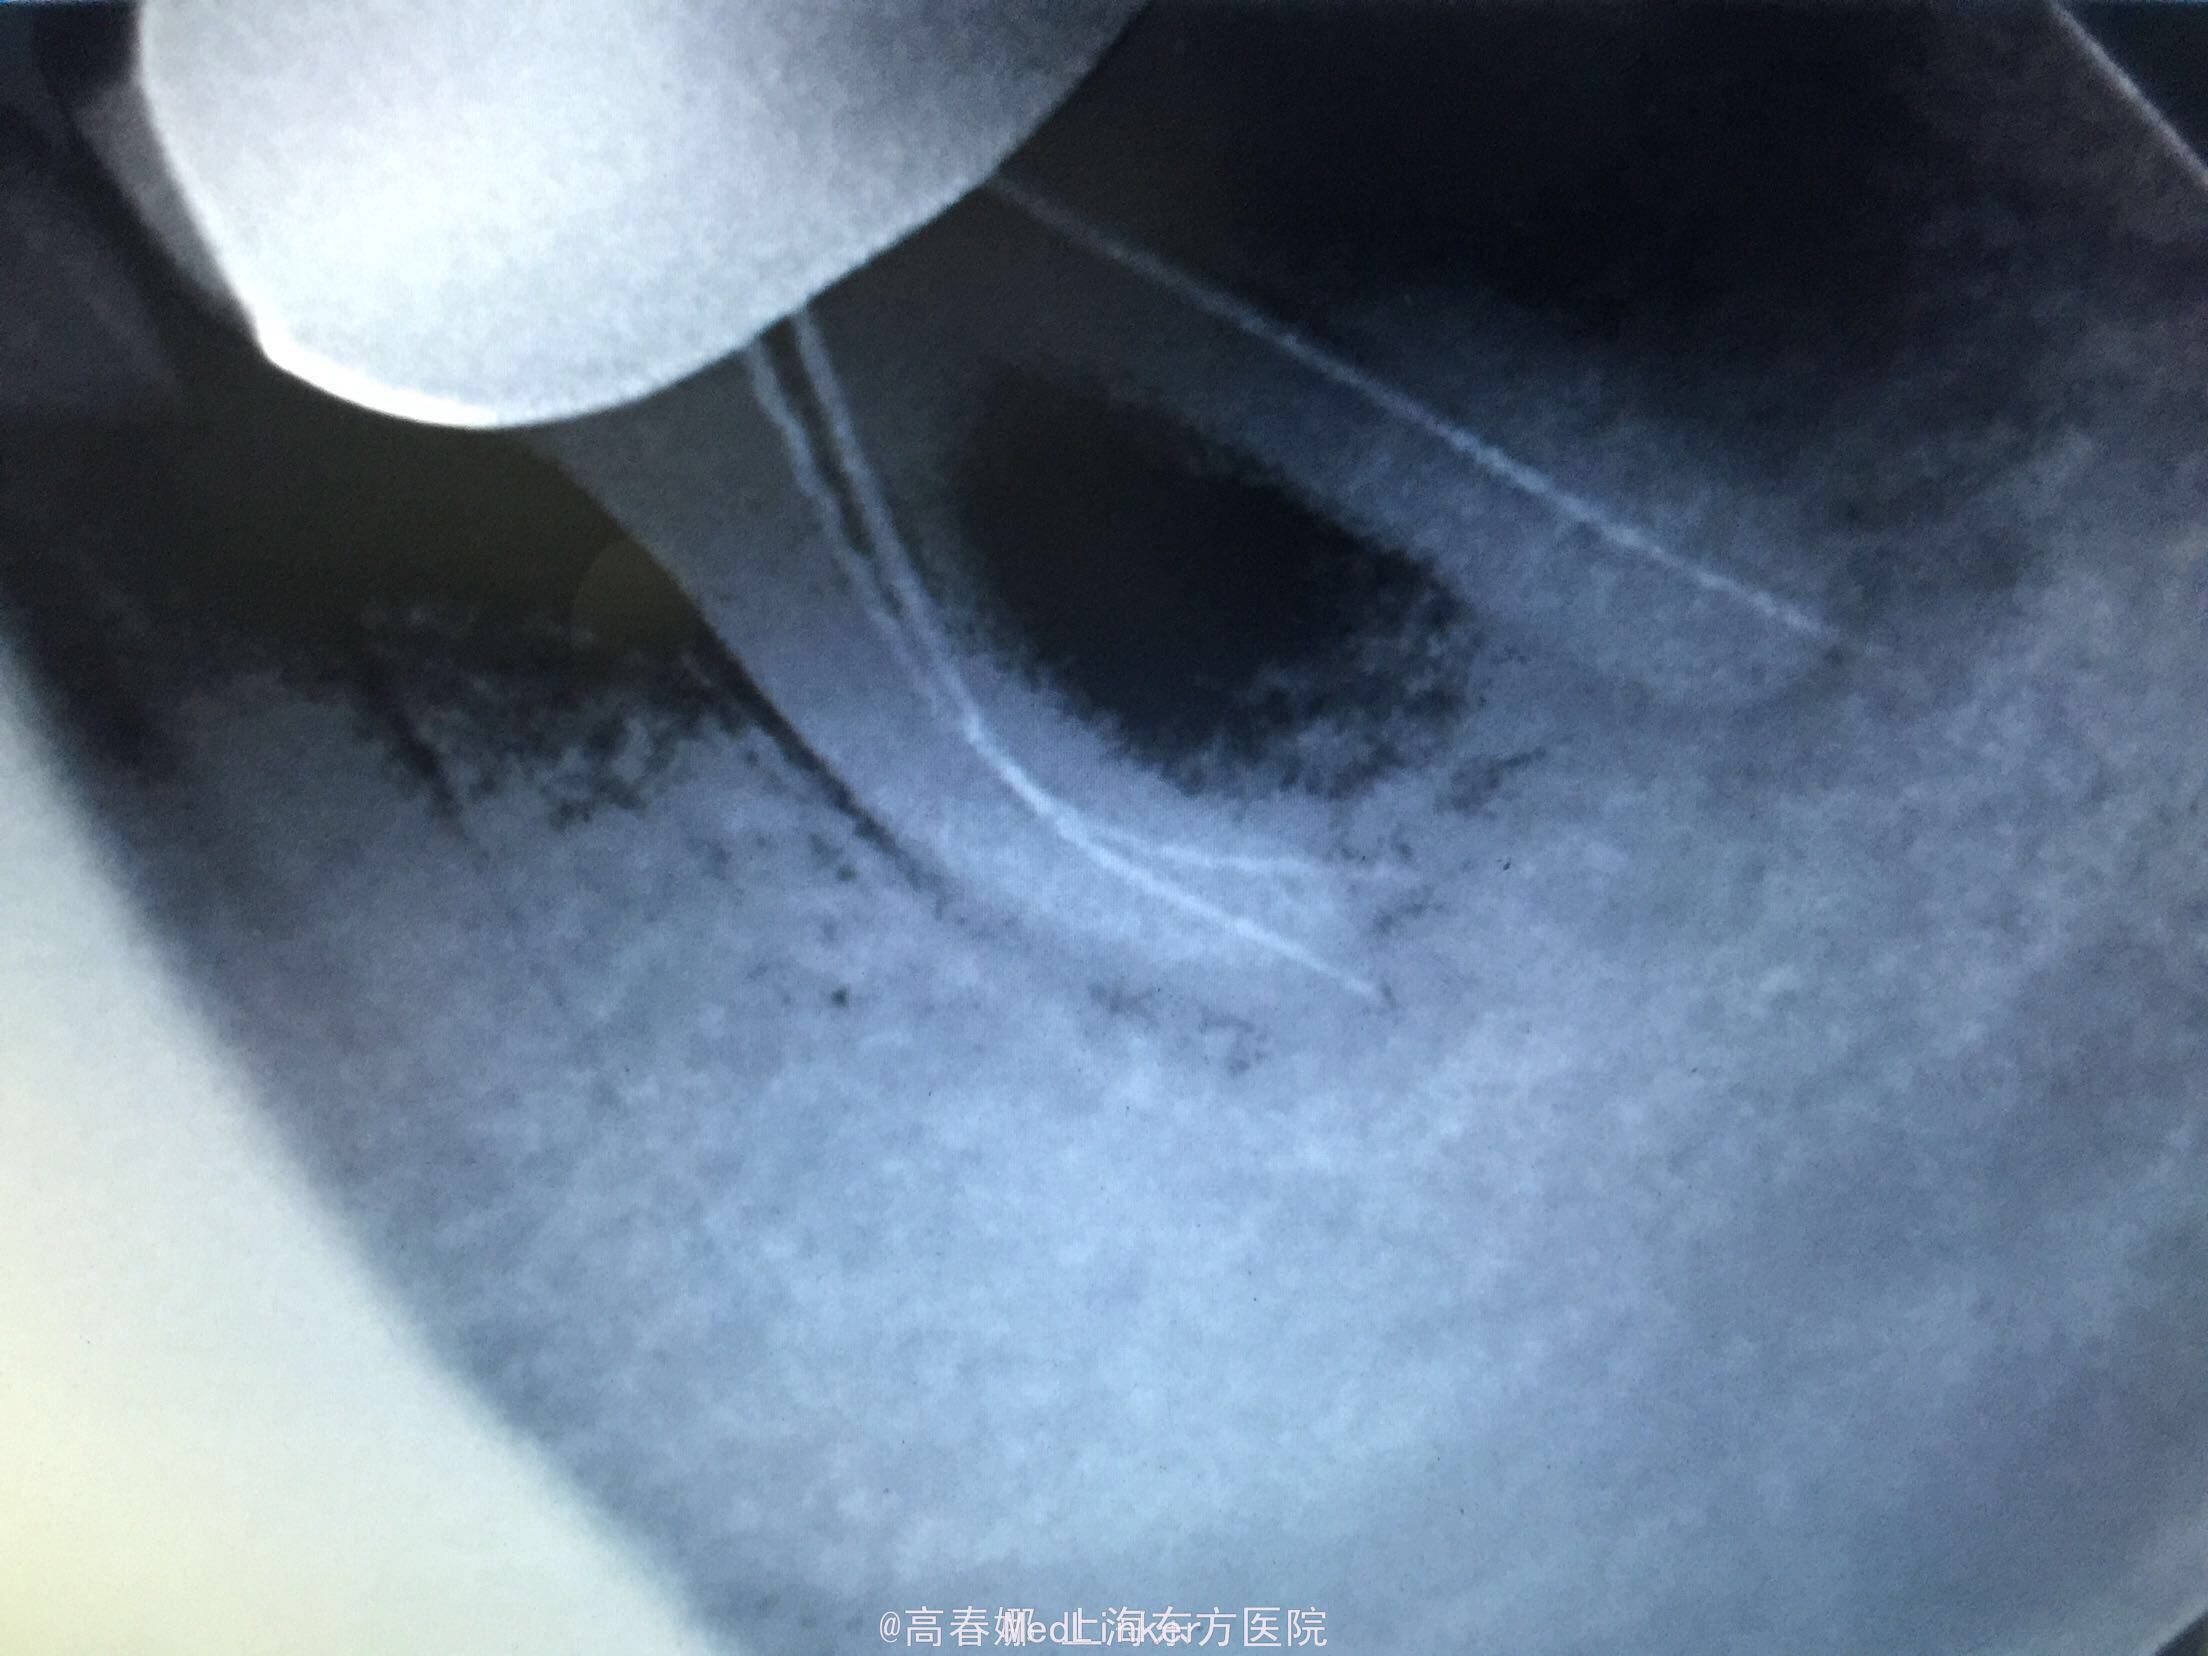

检查:36冠修复,叩诊(+-),松动II度,颊侧牙龈瘘管,牙周袋约3mm,根分叉未探及,冷(-)。 X线示:36根尖区及根分叉区大面积阴影。

随访:三个月复查,牙龈未见明显红肿及瘘管,36扣痛无,松动物。X线示:36根尖及根分叉骨密度增高。